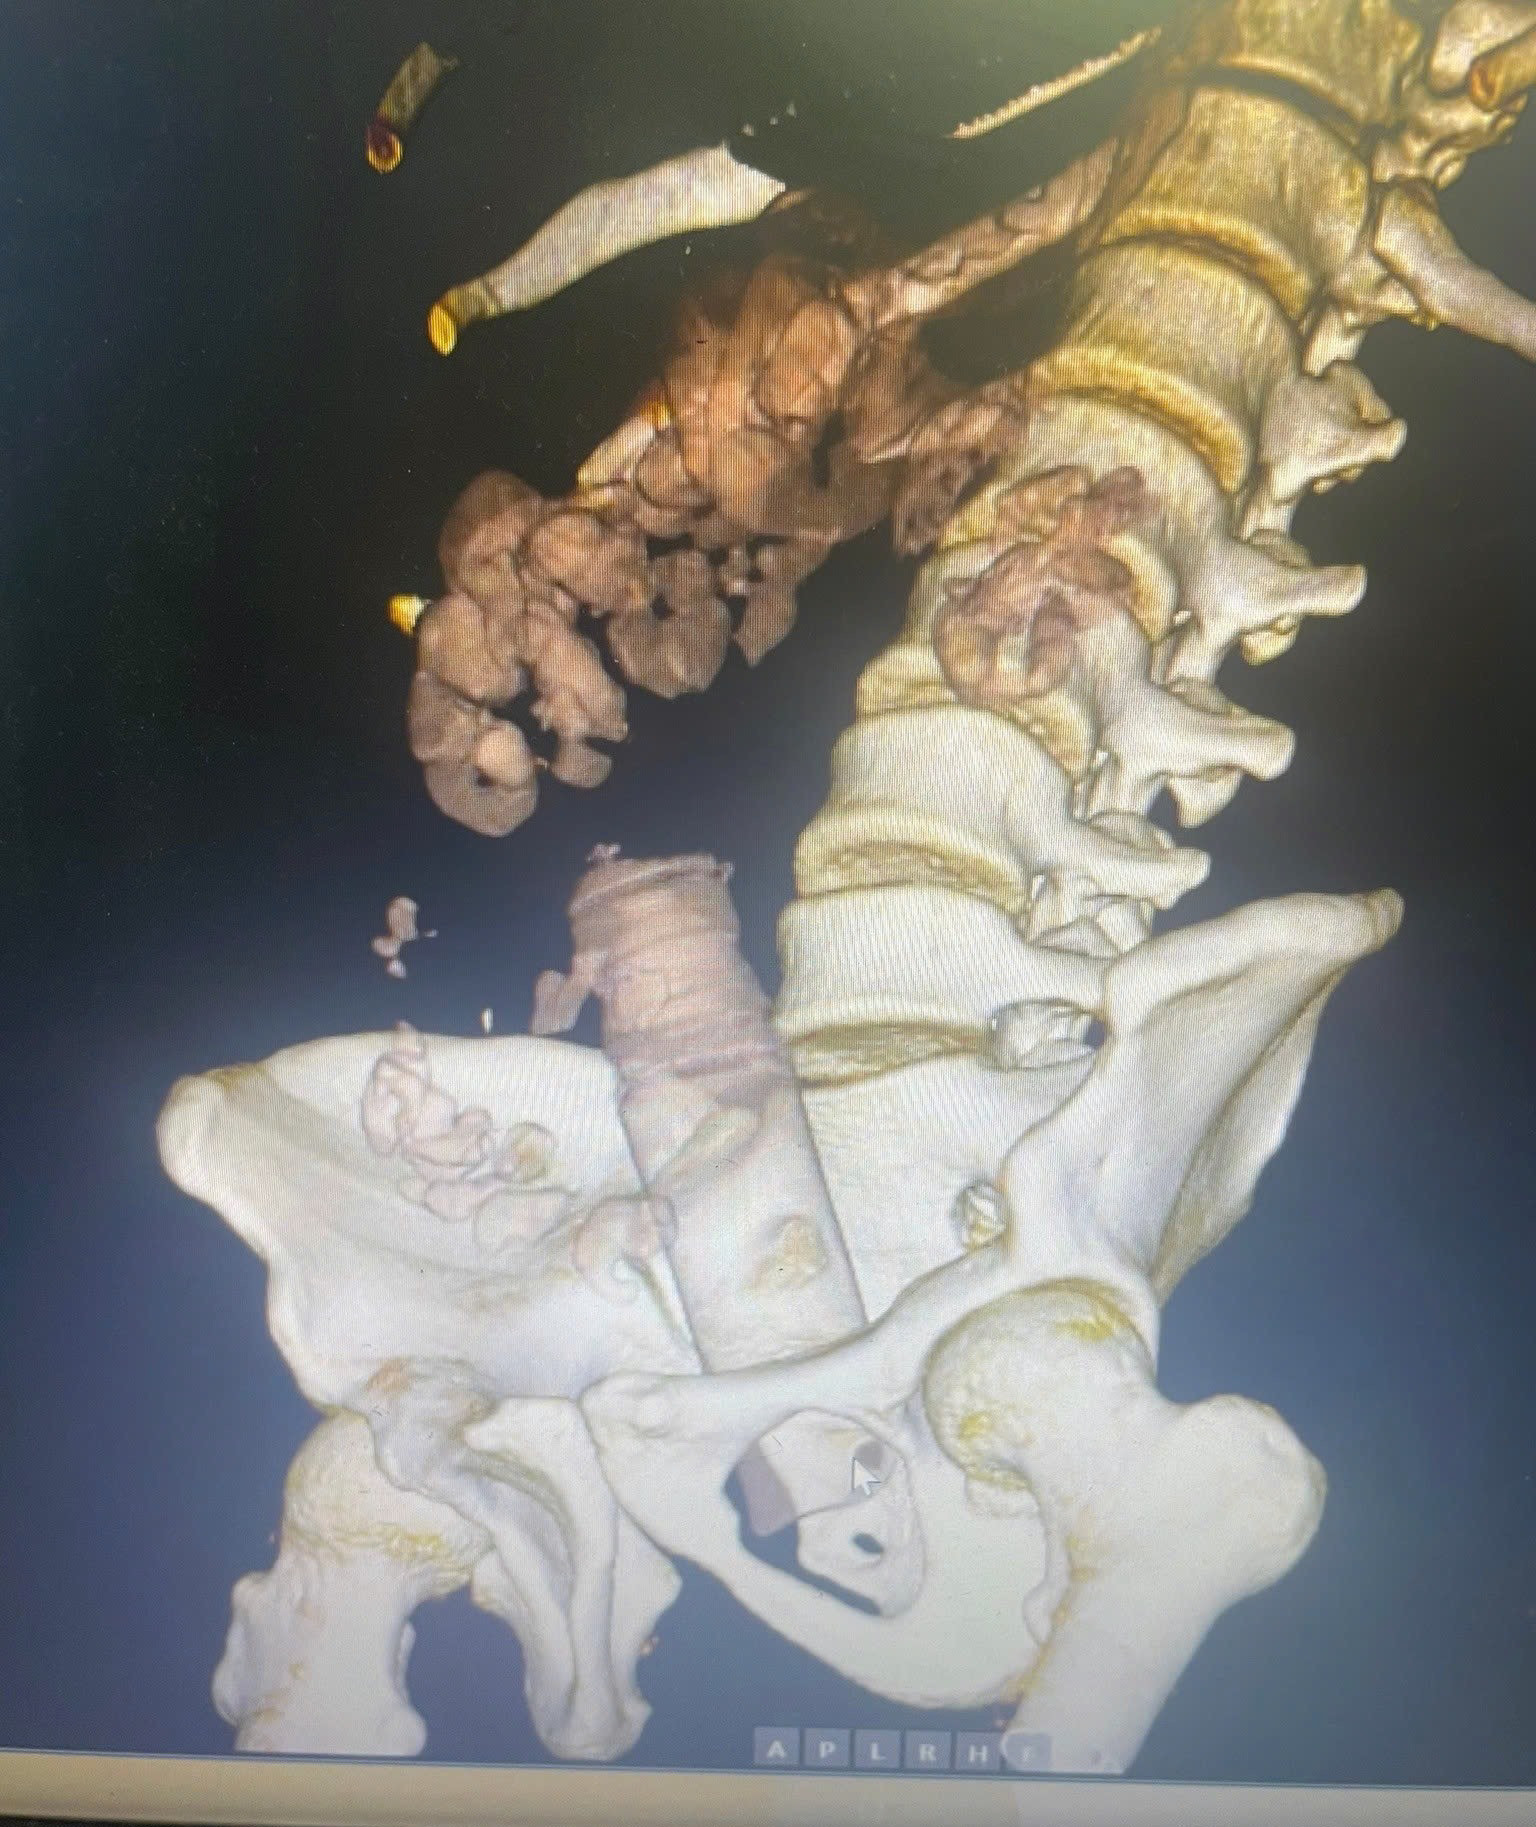

Bệnh viện đã tiến hành chiếu chụp cắt lớp vi tính đánh giá vị trí dị vật và nội soi đại trực tràng để gắp dị vật. Qua phim chụp, bác sĩ cũng hoảng vì dị vât quá lớn chèn vào đường tiêu hóa.